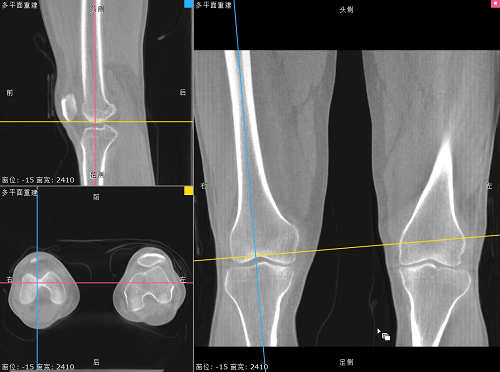

负重位状态下WR-3D MPR多平面重建